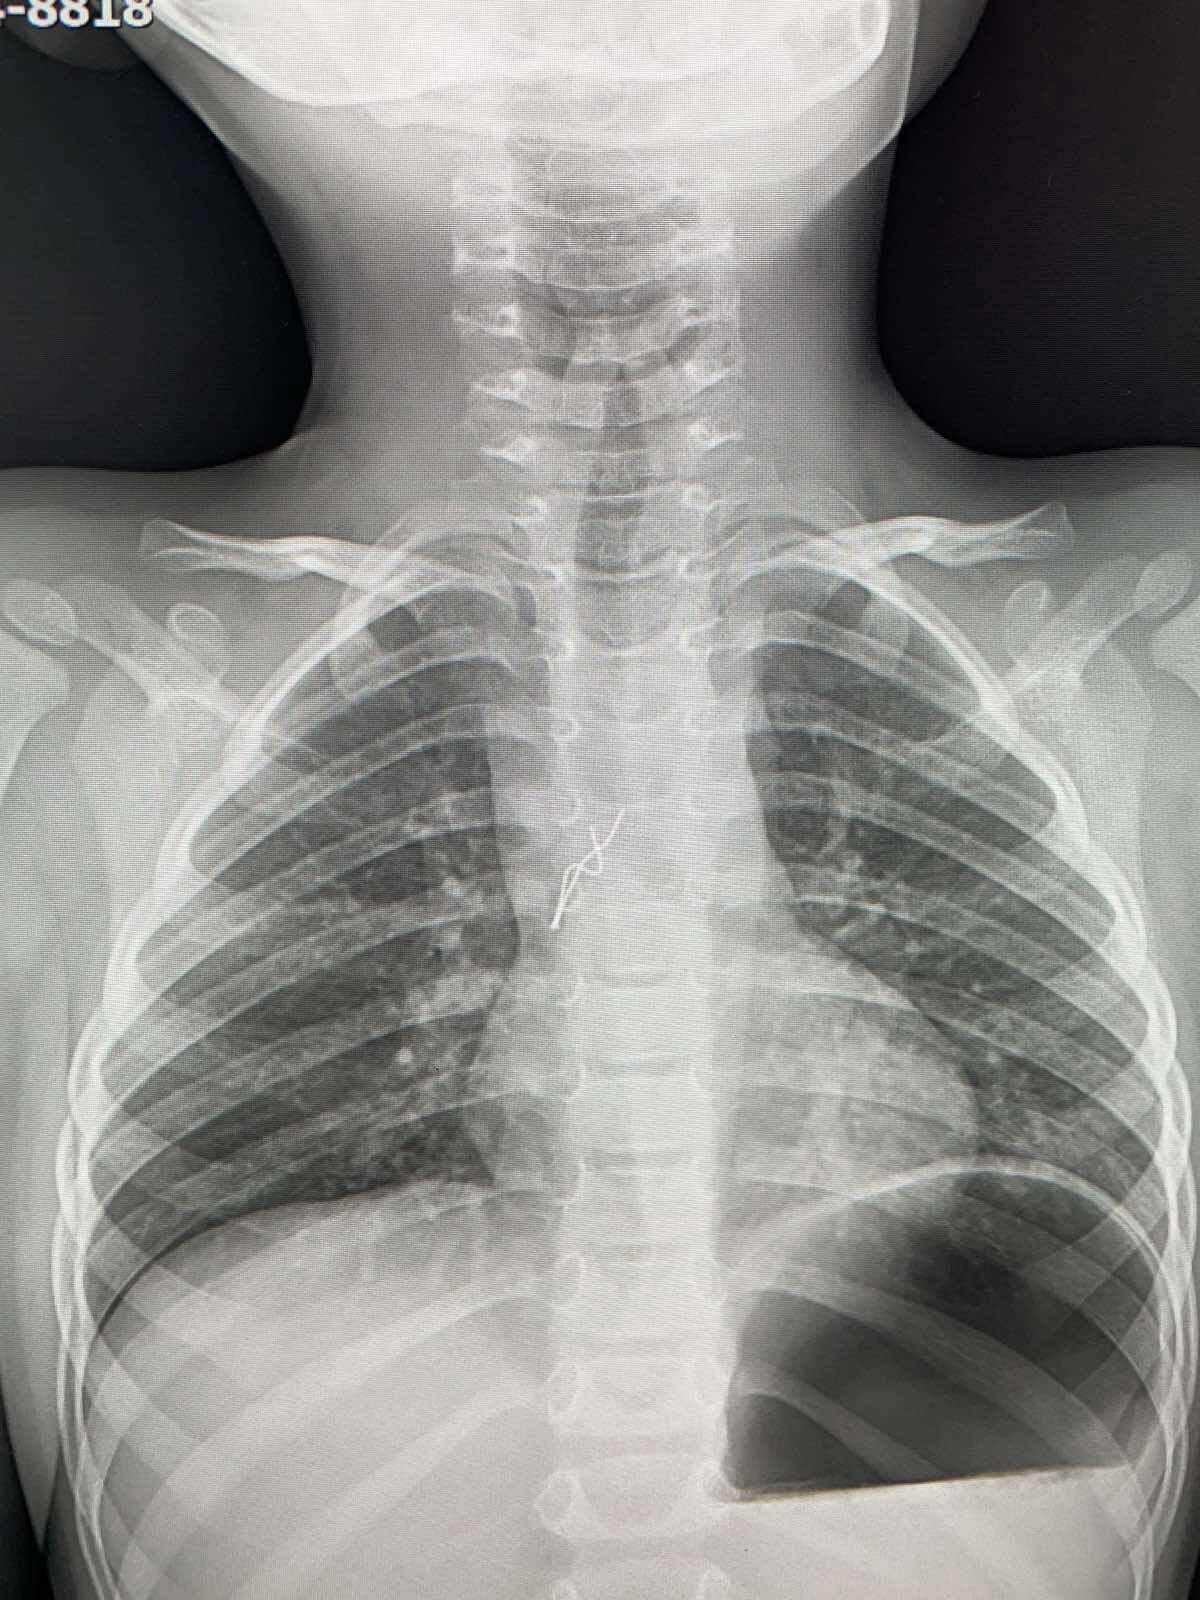

Во Львове из дыхательных путей четырехлетнего ребенка достали лампочку от гирлянды. Врачам удалось сделать все без хирургического вмешательства.

Родители рассказали, что ребенок начал кашлять и задыхаться. Родители сразу вызвали скорую. В больнице сделали рентген и обнаружили инородный предмет.

Торакальный хирург Александр Колодий рассказал, что ему удалось достать лампочку без хирургического вмешательства.

По словам врача, ее усики повредили слизистую оболочку в участке бифуркации трахеи и там появились мелкие кровоизлияния.

"Я схватил усики щипцами, завел их в тубус бронхоскопа и вместе с ним достал лампочку из бронхов ребенка", – сказал Колодий.